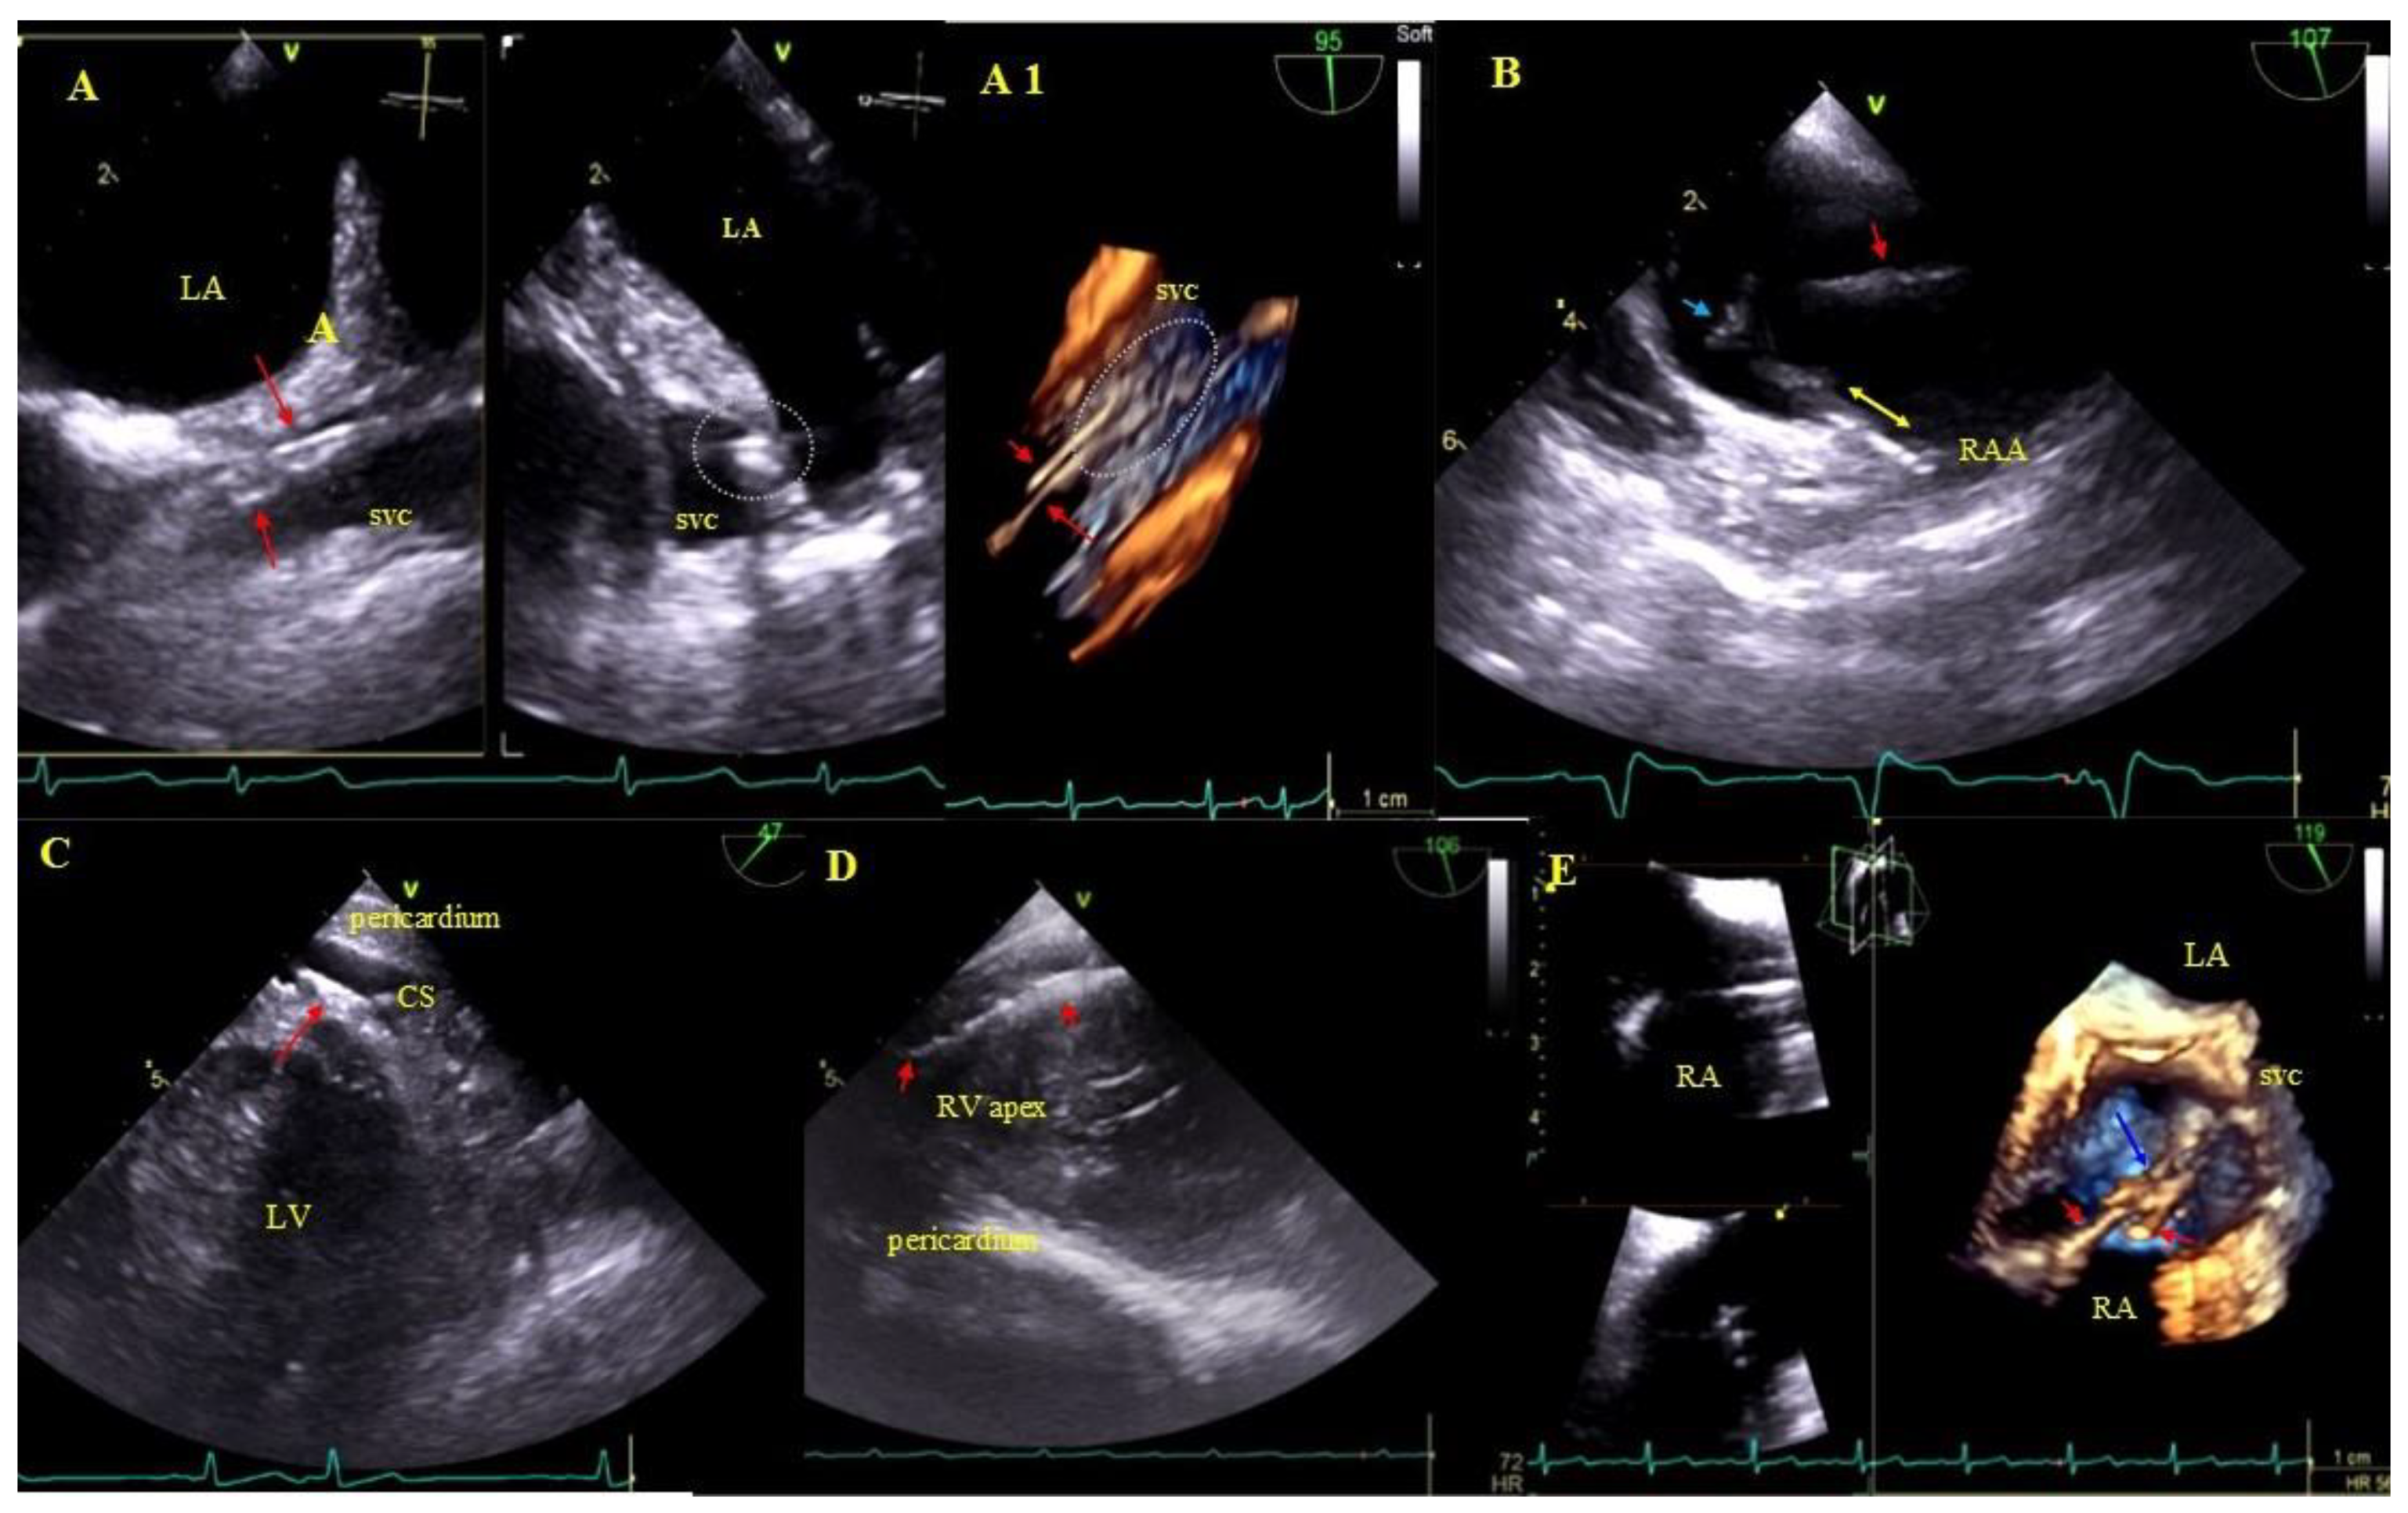

2.5. Echocardiographic Findings Associated with Endocardial Leads: Definition and Classification According to the Anatomy and Characteristic Features

- Factors that may increase the complexity of the extraction procedure and the development of complications but which, per se, do not decrease chances of long-term survival: fibrous tissue binding the lead to the heart structures, lead-to-lead adhesion. The degree of connective tissue overgrowth in response of the endothelium to long-term irritation by the lead depends on implant duration, stiffness and the number of leads, but first of all on patient age (inverse relationship). This phenomenon has been better documented in papers describing lead removal in children and young patients and in adults with leads implanted in childhood [17]. Surprisingly, the current study found that various forms of connective tissue overgrowth (fibrous tissue binding the lead to the heart structures, lead-to-lead adhesion, lead thickening, scar tissue surrounding the lead) were associated with better long-term survival, although based on previous observations [31,32], connective tissue overgrowth was a predictor of TLE technical difficulty and major complications. This proves that the course of the procedure does not affect prognosis after TLE.

- Perforation, penetration—as was the case of lead loops, perforation/penetration was the main or accompanying indication for lead extraction (most of them were “dry” and caused lead dysfunction or, less frequently, it was an incidental finding or the cause of fluid accumulation in the epicardial space). All perforating/penetrating leads were replaced, thus eliminating their influence on survival and future quality of life. Similar to lead loops, perforations in univariate and multivariate Cox analysis of Model 1 were significantly related to better survival odds.